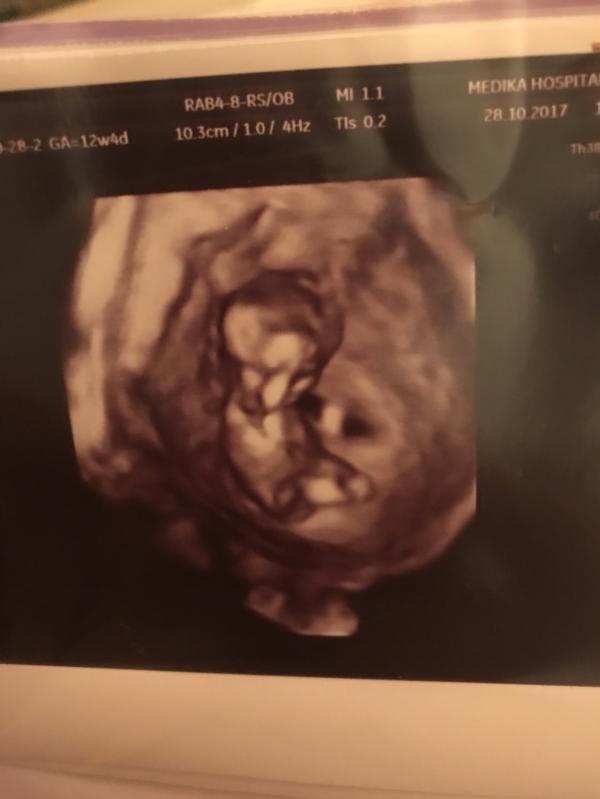

Вот наше чудо❤️🙏🏻 Спасибо Богу за такую возможность, за эти несравнимые чувства😭🙏🏻 Все чаще встречаю людей которые не могут зачать ребёнка😔 И становится так грустно и помочь ничем не может только малитвами🙏🏻 Моя первая беременность прервалась на 13-14 недели ( замершая беременность) депрессия ненавидела весь мир почему я? За что? Почему? Как? И не знала как прожить этот момент ооочень тяжелый😔 И вот ровно через год в августе 2016 аборт и в августе 2017 я забеременела ❤️ Иншаллах все будет хорошо коне...